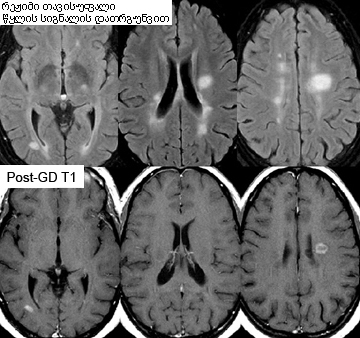

უნდა ჩატარდეს მაღალტექნოლოგიურ (უმჯობესია 3T,თუმცა 1,5T მისაღებია) მაგნიტზე, ინტრავენური გადოლინიუმის კონტრასტით.[Figure caption and citation for the preceding image starts]: სითხეში შესუსტებული ინვერსიული აღდგენის (FLAIR) გამოყენებით მიღებული ღერძული მაგნიტური რეზონანსული გამოსახულება, რომელიც აჩვენებს ტიპურ დაზიანებებს გაფანტული სკლეროზის დროს, პერივენტრიკულურ რეგიონებში. შედარებად ჭრილებში, რომლებშიც გამოყენებულია საკონრასტო ნივთიერება გადოლინიუმი, ასახულია ჰემატოენცეფალური ბარიერის დარღვევა/აქტიური ანთება 2 დაზიანებულ კერაში. FLAIR მეთოდით აღმოჩენილი დაზიანებები, რომლებიც საკონტრასტო ნივთიერებაზე არ რეაგირებს, მაღალი ალბათობით, უფრო ძველი დაზიანებებია. ასეთ დაზიანებებში აღინიშნება გლიოზისა და დაბალი ხარისხის ქრონიკული ანთებისა და დეგენერაციის კომბინაცია.From the collection of Dr Lael A. Stone [Citation ends].

რეკომენდებულია საგიტალური სამგანზომილებიანი (3D) სითხით შესუსტებული ინვერსიული აღდგენა (FLAIR) მრავალფუნქციური რეკონსტრუქციის ფუნქციით. ღერძული T2 შეწონილი FLAIR გამოიყენეთ, თუ ეს მოდული არ არის ხელმისაწვდომი.[3]

გაფანტული სკლეროზით დაავადებულ თითქმის ყველა პაციენტს აქვს თავის ტვინის ტომოგრაფიით უვლინდება პათოლოგია, თუმცა ინტერპრეტაცია შეიძლება რთული იყოს. შედეგებს განიხილავენ სპეციალისტები, რომლებსაც იციან გაფანტული სკლეროზის MRI მახასიათებლები.